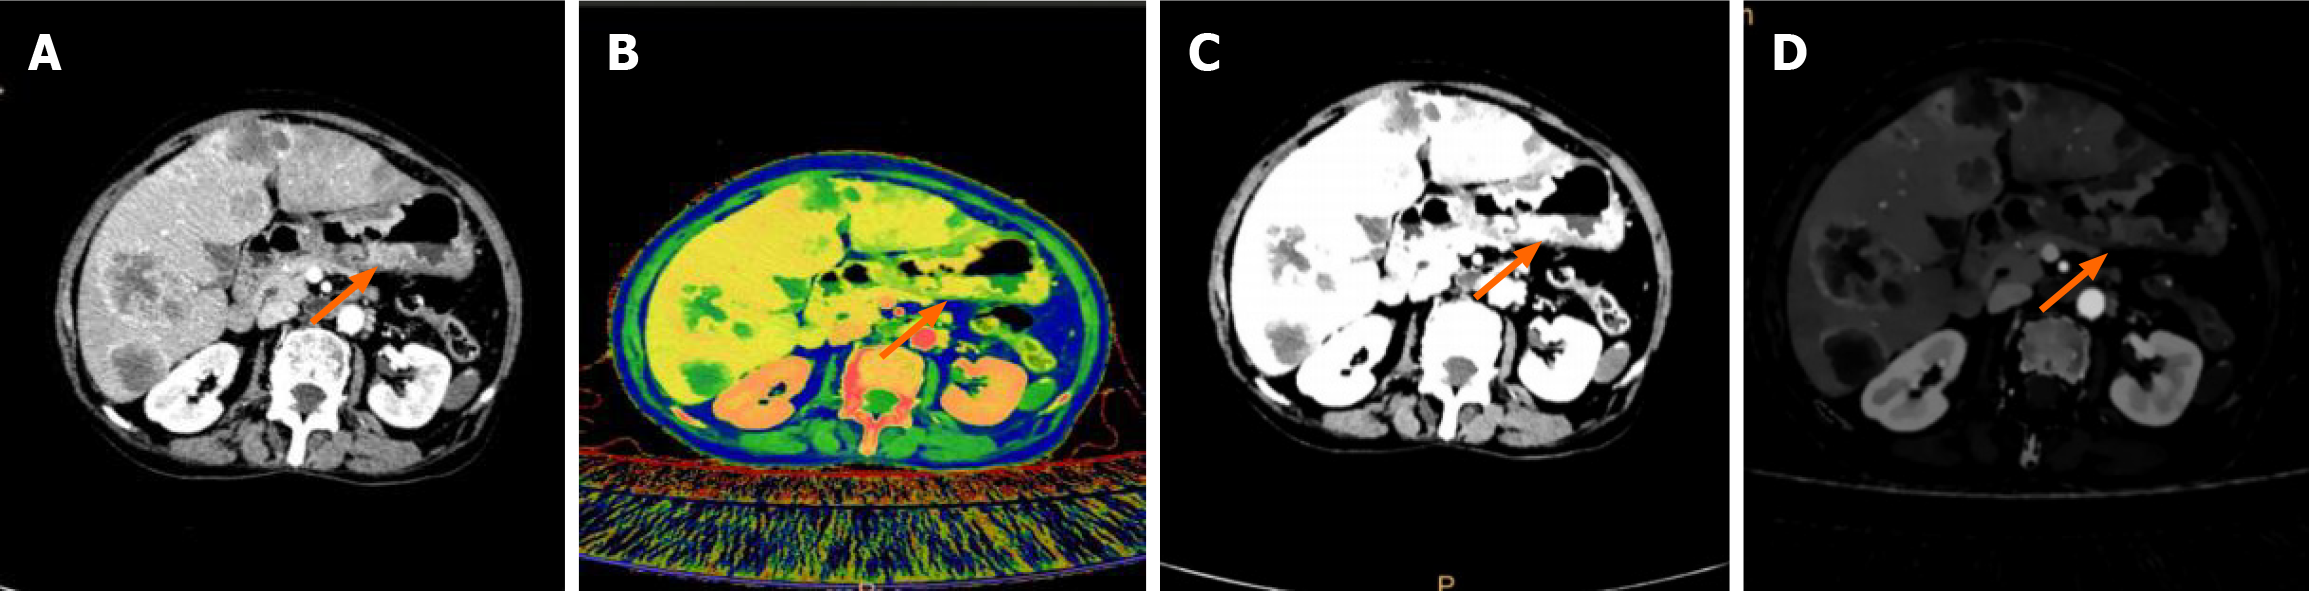

DLCT example images of a 74-year-old female GC patient are shown in Figure 2. Accurate assessment of TP53 mutations and Ki-67 levels can facilitate the selection of appropriate treatment strategies for GC. A study reported that a model incorporating clinical features and DLCT-derived quantitative parameters showed significantly higher performance in predicting TP53 expression compared to clinical and conventional CT-based models[14]. Several studies have indicated that quantitative parameters derived from spectral CT can differentiate between varying levels of Ki-67 in GC, indicating that Ki-67 status is positively correlated with IC and NIC in the VP[15,16]. The therapeutic benefits of immunotherapy vary depending on the microsatellite instability (MSI) status of patients. Consequently, developing novel techniques for assessing the MSI status of patients with GC is necessary. Zhu et al[17] reported that NIC-VP derived from spectral CT exhibited the highest predictive efficacy in discriminating MSI status. A predictive model incorporating DLCT parameters (NIC-VP, Zeff-VP, and λHU-VP), tumor location, and lymph node stage evaluated from DLCT images (N-CT stage) showed superior accuracy in predicting the MSI status of patients with GC. This model may serve as a valuable tool for postoperative risk stratification.

Figure 2

Figure 2 Gastric cancer and dual-layer spectral computed tomography images. A: Conventional computed tomography image in the arterial phase (AP); B: Effective atomic number in the AP; C: Virtual monochromatic image; D: Iodine concentration in the AP.